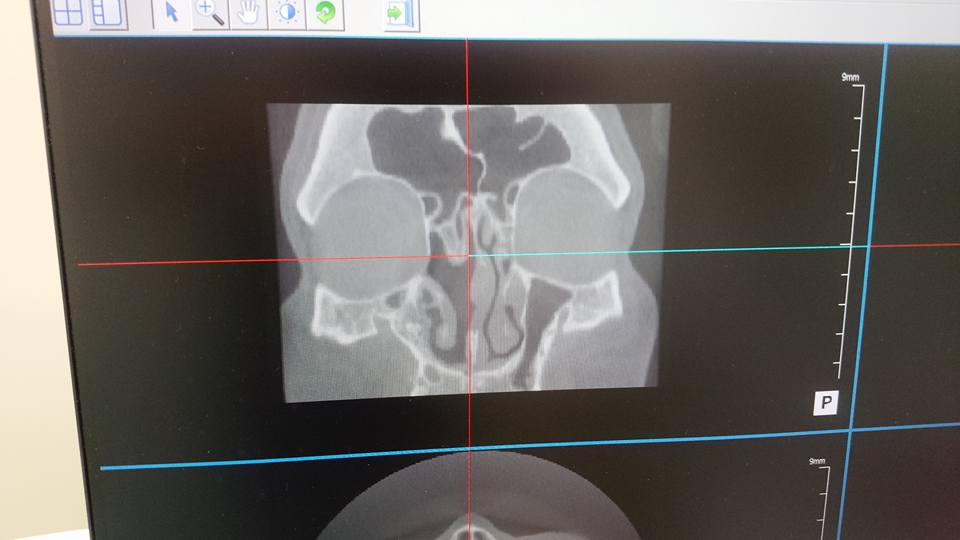

・・・しかし、手術の甲斐はあった 手術前には真っ白だった右の上顎洞 手術後に撮影したCTでははっきり判るくらい上顎洞がスッキリしている

お蔭で息がしやすい